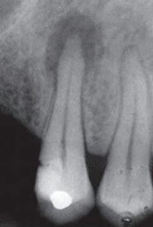

白箭头指示上颌窦牙龈瘘

1)根尖周炎:是指根尖部牙周膜、牙骨质、牙槽骨的炎症;

2)根尖囊肿,也称神经根囊肿,由牙齿感染引起;通常见于30-60岁,主要症状是深龋洞,牙齿变色,反复出现牙龈脓包等。